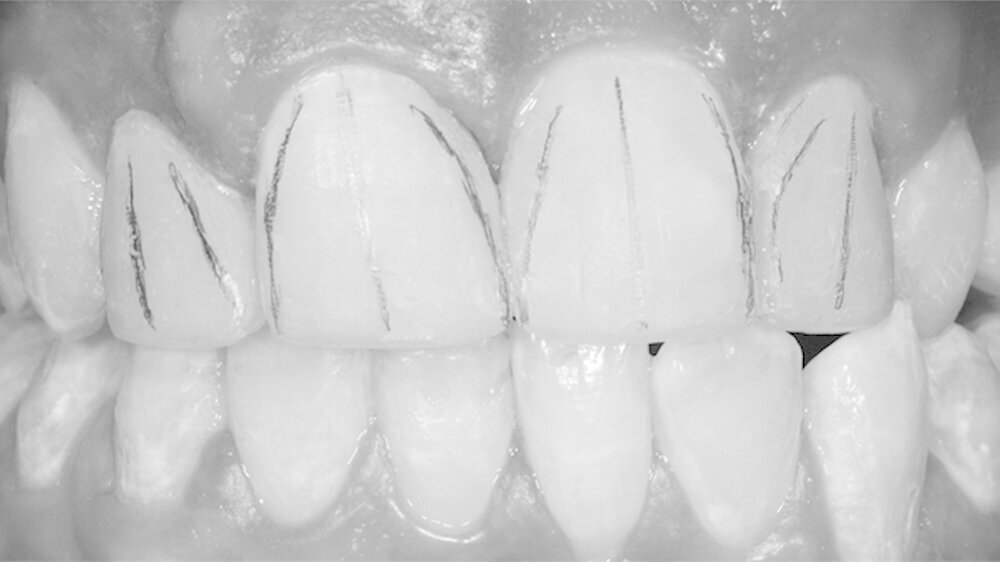

Bei diesem komplexen Fall musste mit Hilfe eines Wax-up ein Silikonschlüssel angefertigt werden, um die Formen aller Frontzähne sicher modifizieren zu können.Ceram.X Duo ermöglichte eine optimale Schichttechnik mit verschiedenen Opazitäten.

Das Alter des Patienten (17 Jahre) spielte hier eine wichtige Rolle. Der Behandlungsplan sollte möglichst keine indirekten Restaurationen beinhalten und eine eventuelle Weiterentwicklung der dentalen Situation berücksichtigen. Deshalb wurde eine minimal-invasive Lösung gewählt, und die beschriebene Schichttechnik erschien angebracht.